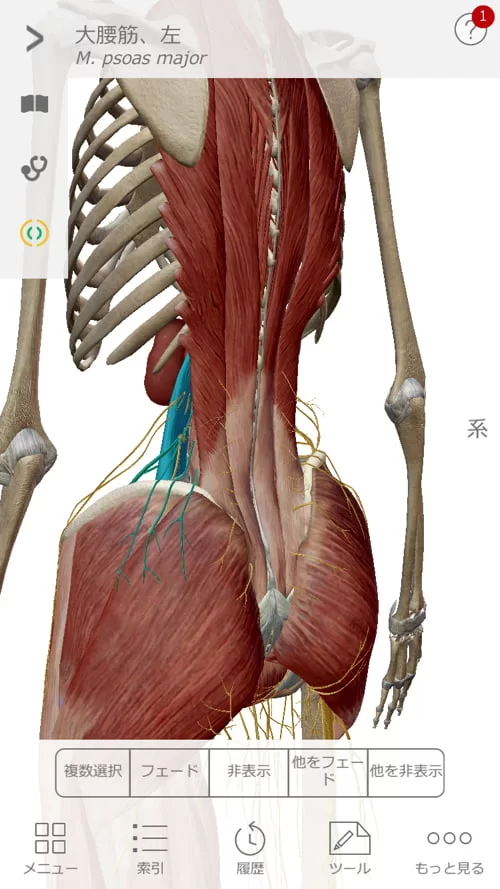

そして背骨と骨盤の前側を繋いでいる筋肉の硬直を解きます。

大腰筋や腸骨筋類。